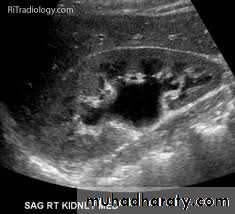

Ultrasound findings

1-Dilatation of the P.C.S. appears as multilocular fluid collection within central echo complex.-With more severe distention, dilated calyces appear as

Multiple cysts but communicating with each other unlike true cysts.

2-Stones larger than 5mm are easily seen on US but smaller ones may be missed.

-They produce intense echoes (hyperechoic) and cast acoustic shadows.